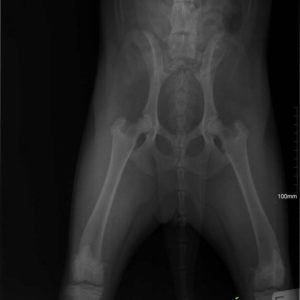

Zora túl van a műtéten és 5 nap után újra velünk van a menhelyen! A kedve jó, nincsenek fájdalmai és reméljük a 2 hónap pihenő után végre felszabadultan játszhat majd a többiekkel!